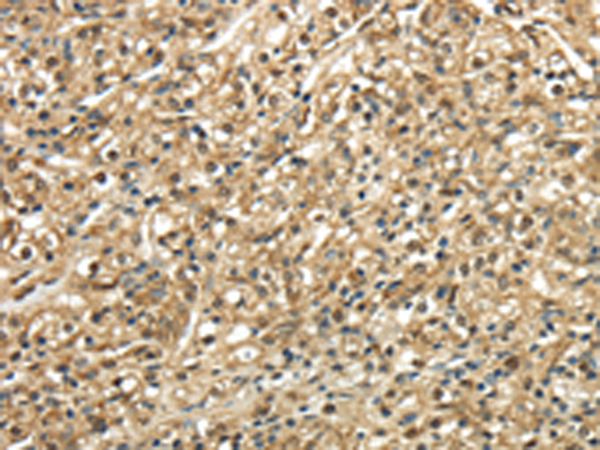

分类: 科研抗体货号: P08927别名: TRP14; TXNL5应用: IHC反应种属: Human, Mouse